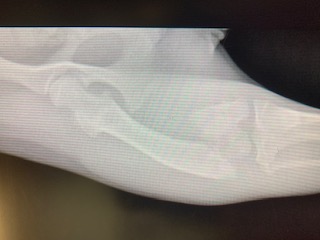

Marigold was found severely injured and was taken to the Humane Society of Parkersburg after being likely hit by a car. At only 8 months old, the diagnosis of a broken femur was devastating, and expensive.

The Humane Society of Parkersburg reached out to Dr. Gandolf, who was able to surgically repair the femur- at a cost they could afford! The Animal Care Hospital of Reynoldsburg generously offered their operating room to help make this possible. This affordable alternative allowed the Humane Society of Parkersburg to save Marigold’s leg!